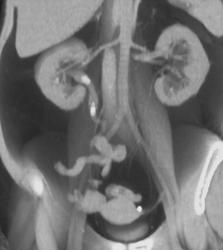

Right Hypervascular Renal Cell Carcinoma